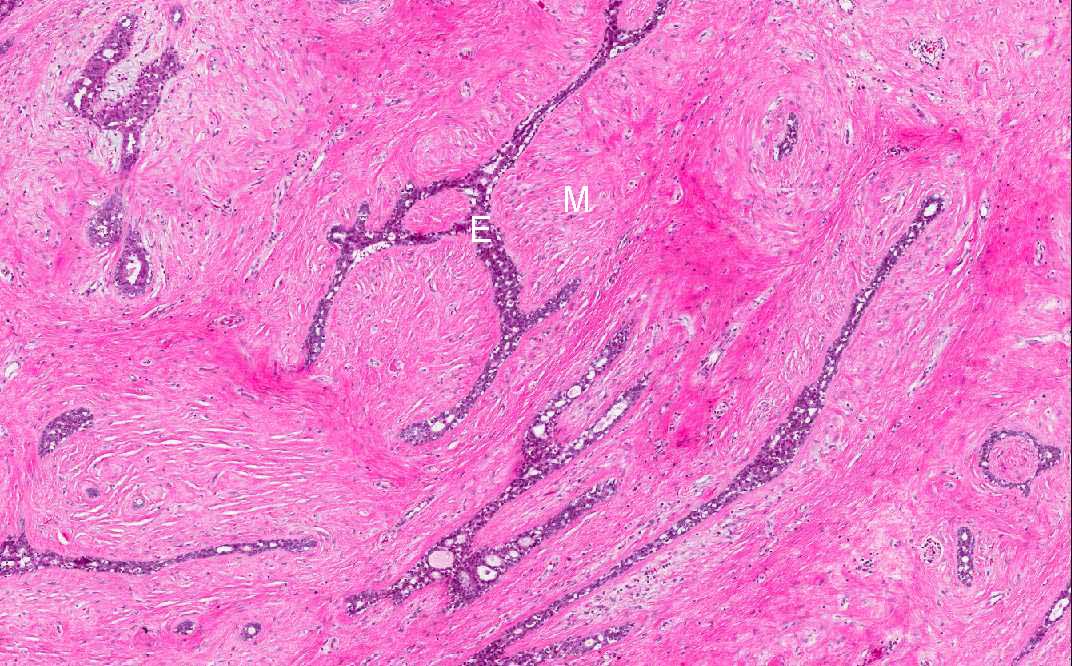

Area 1: In this area you can see both the epithelial component (E) and the mesenchymal component (M). The epithelial component lacks nuclear features indicative of malignancy. The mesenchymal component has low cellularity and with bland nuclei free of enlargement, pleomorphism, prominent nucleoli, or hyperchromatism.

Area 1: Epithelial component does not show any features suggestive of dysplasia or malignancy. The epithelium remains single cell layer.

Area 1: Low cellularity and fibrotic change in the mesenchymal component.